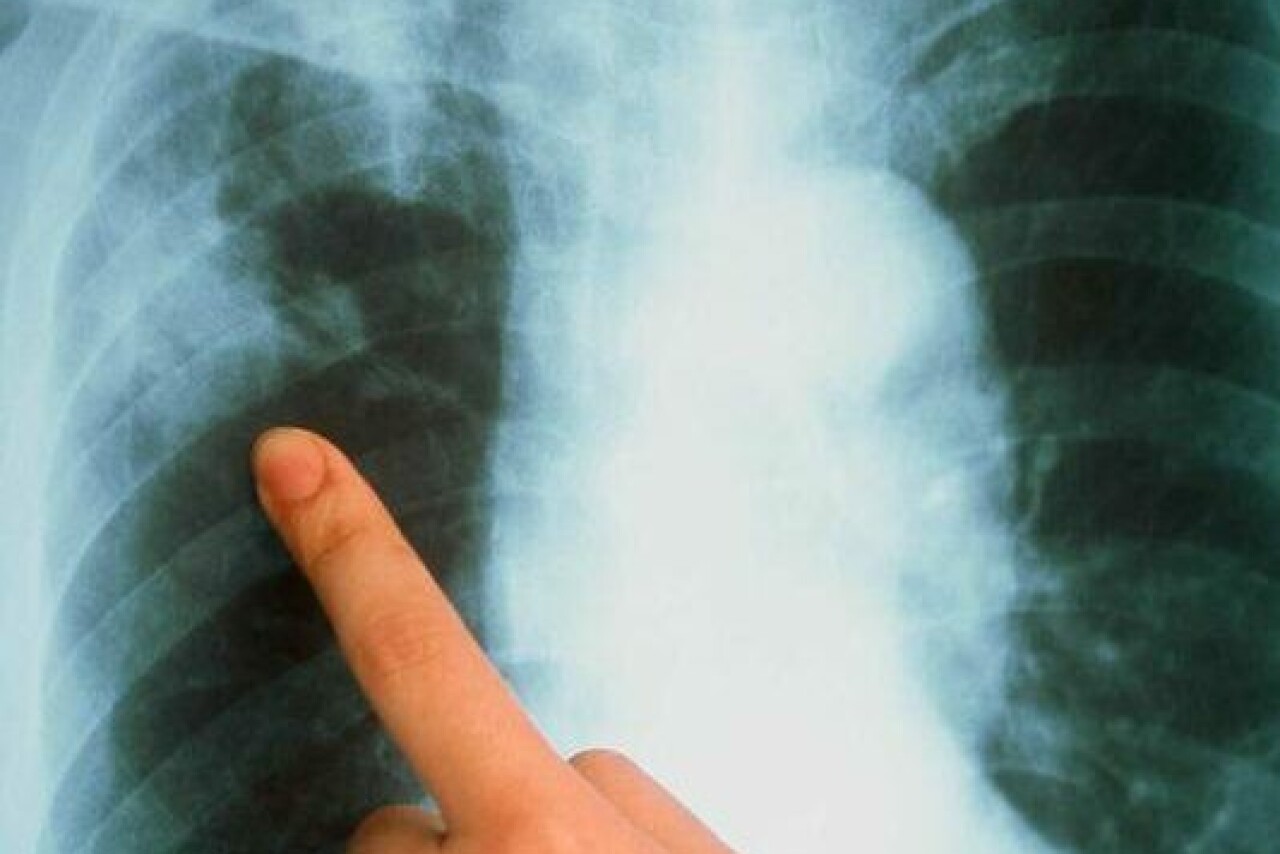

Многие тяжёлые и смертельно опасные болезни, такие как рак легких и туберкулёз, могут долгое время протекать скрытно, не вызывая видимых изменений в состоянии здоровья человека. Часто кашель, одышка, повышение температуры, снижение веса и общая слабость проявляются на запущенной, а иногда неизлечимой стадии болезни. Регулярные флюорографические обследования способны выявить болезнь на ранних стадиях, что позволяет полностью излечиться и вернуть привычный образ жизни.

Медики утверждают, что туберкулёз можно вылечить, если заболевание будет выявлено на ранней стадии. Лечение может занимать от полугода до двух лет и зависит от формы туберкулёзного процесса. Успех лечения зависит как от усилий врача, так и от приверженности к лечению самого пациента.

С докладом о состоянии противотуберкулёзной помощи в Дагестане выступила заместитель главного врача Республиканского противотуберкулёзного диспансера Фаина Тагирова. Цифры обнадеживают: за 7 месяцев 2024 года было выявлено 386 больных, что означает показатель заболеваемости 11,9 на 100 тысяч населения. Для сравнения, за аналогичный период прошлого года было 472 человека (14,7%). Динамика показывает устойчивое снижение числа больных.

Наиболее высокие показатели заболеваемости зафиксированы в Цунтинском, Кизилюртовском и Хасавюртовском районах, а также в Кизилюрте, Южно-Сухокумске и Буйнакске.

К сожалению, болеют как взрослые, так и дети. Лидером по количеству заболевших остаётся Махачкала с 25 случаями, за ней следуют Хасавюрт (5) и Кизилюрт (2). Важно отметить, что профилактика, в том числе рентгенологические методы обследования, играют ключевую роль в борьбе с туберкулёзом.